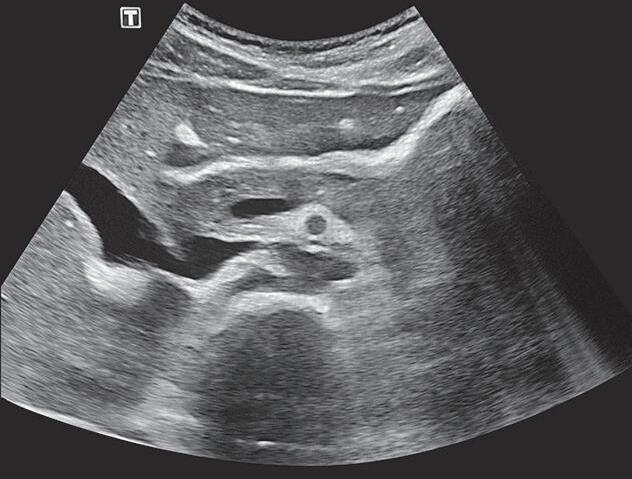

Fig. 4-9. Vasos epigástricos inferiores. A hérnia inguinal direta fica medial aos vasos e a indireta lateral aos vasos.